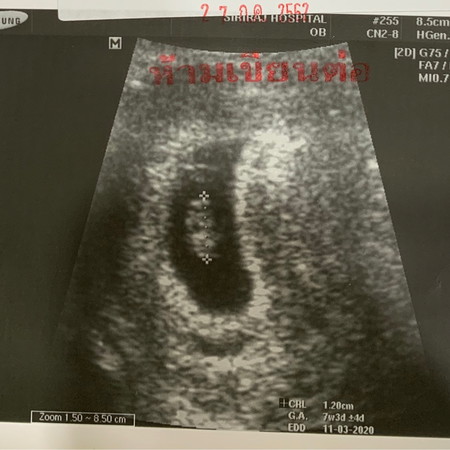

เผยโฉมแล้วจ้า 7 สัปดาห์ 5 วัน ซาวด์ทางหน้าท้อง (ลุ้นมากกก กลัวไม่เห็น เพราะเท่าที่หาข้อมูลมา ซาวด์ทางหน้าท้องก่อน 9 สัปดาห์ จะเห็นตัวอ่อนและการเต้นของหัวใจค่อนข้างยากหน่อย ทางช่องคลอดจะง่ายกว่า) .. แต่เหมือนหนูคงรู้ว่าแม่กังวล หนูก็เลยปรากฏมาให้แม่เห็น คุณหมอแกล้งด้วย คุณหมอบอกว่า "ไม่เจอตัวอ่อนนะครับ .. ไม่เจอว่าเป็นแฝดน่ะครับ" .. แม่ใจหายแว้บไปเสี้ยววิเลยจ๊ะลูกจ๋า~ อีกคำพูดที่ดีใจที่ได้ยินคือ "หัวใจเต้นปกติดีครับ" ได้ยินแล้วชื่นใจที่สุดเลยค่ะ ลืมความทรมานของการแพ้ท้องไปเลย(แปปนึง) แม่จะดูแลหนูให้ดีที่สุดทุกวินาทีของชีวิตแม่ อยู่กับแม่ตลอดไปนะลูก❤️ ปล; ตอนซาวด์ ก็พยายามจะมองจออัลตราซาวด์ให้รู้เรื่องแบบคุณหมอ แต่ไม่ได้จริงๆค่ะ งงไปหมดเลย หมอบอกนี่เห็นมั้ยๆ อันนี้นี่นะๆ เราก็ได้แต่งึ่กงั่กๆ ในใจคือ 'อะไรฟว้าาาา' 55555